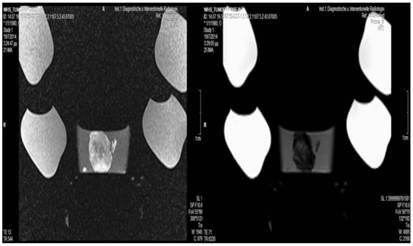

Figure 12

Cisplatin and Microwave; T1 sequence: Heterogeneous appearance in the central part of the tumor, low intensity indicates necrosis. T2 sequence: High signal intensity indicates necrosis. White arrow indicates area where the microwave spike was inserted.

Tumor necrosis and apoptosis were the major purposes of our study. Survival was also recorded. Our records and MRI findings indicate that a major toxicity was observed in the group where cisplatin, lipiodol and microwave were applied. None of the animals survived more than a week. Moreover; hemorrhage apart from necrosis was observed inside the tumors. Survival was the following for the groups: microwave (25days) ≥ cisplatin (22 days) > control (20 days) > lipiodol (16 days)> microwave plus lipiodol (16 days) > cisplatin plus lipiodol (12) > cisplatin plus microwave (12 days) > lipiodol plus cisplatin plus microwave (5 days). (Figure 5-12.)